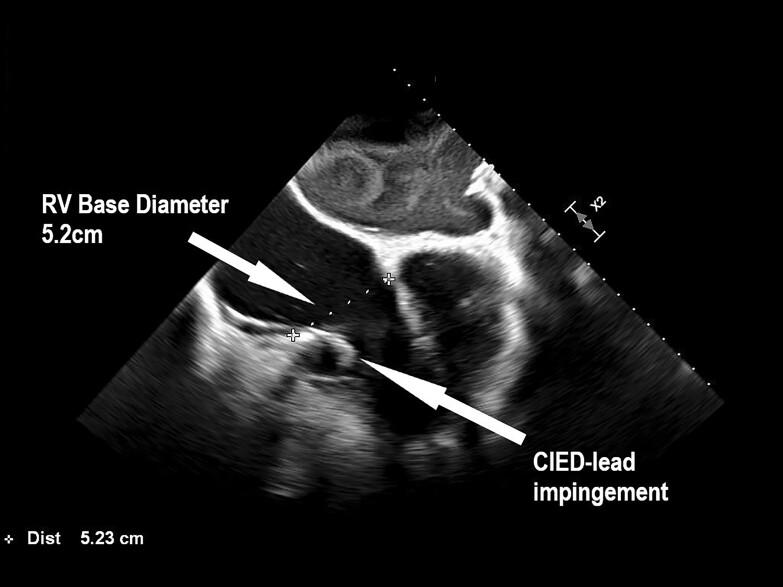

A 69-year-old woman presented with recurrent hospital admissions for right heart failure refractory to medical therapy, on the background of a single-chamber permanent pacemaker (Biotronik) implanted 6 years ago for tachycardia-bradycardia syndrome. Transoesophageal echocardiography identified severe TR which was predominantly CIED-induced from a lead impingement of the posterior tricuspid valve (TV) leaflet preventing adequate leaflet coaptation. This had progressed to cause a degree of secondary functional TR. The patient underwent pacing lead extraction followed by epicardial lead placement via minithoracotomy, with significant symptomatic and echographic improvement of TR.

一名69岁女性因右心衰竭反复住院,药物治疗无效,6年前因心动过速-心动过缓综合征植入单腔永久起搏器(百多力)。经食管超声心动图检查发现严重TR,主要由CIED引起,因导线压迫三尖瓣(TV)后叶,导致瓣叶无法充分对合。这已发展为一定程度的继发性功能性TR。患者接受了起搏导线拔除,随后通过小切口开胸进行心外膜导线植入,TR的症状和超声心动图表现有显著改善。